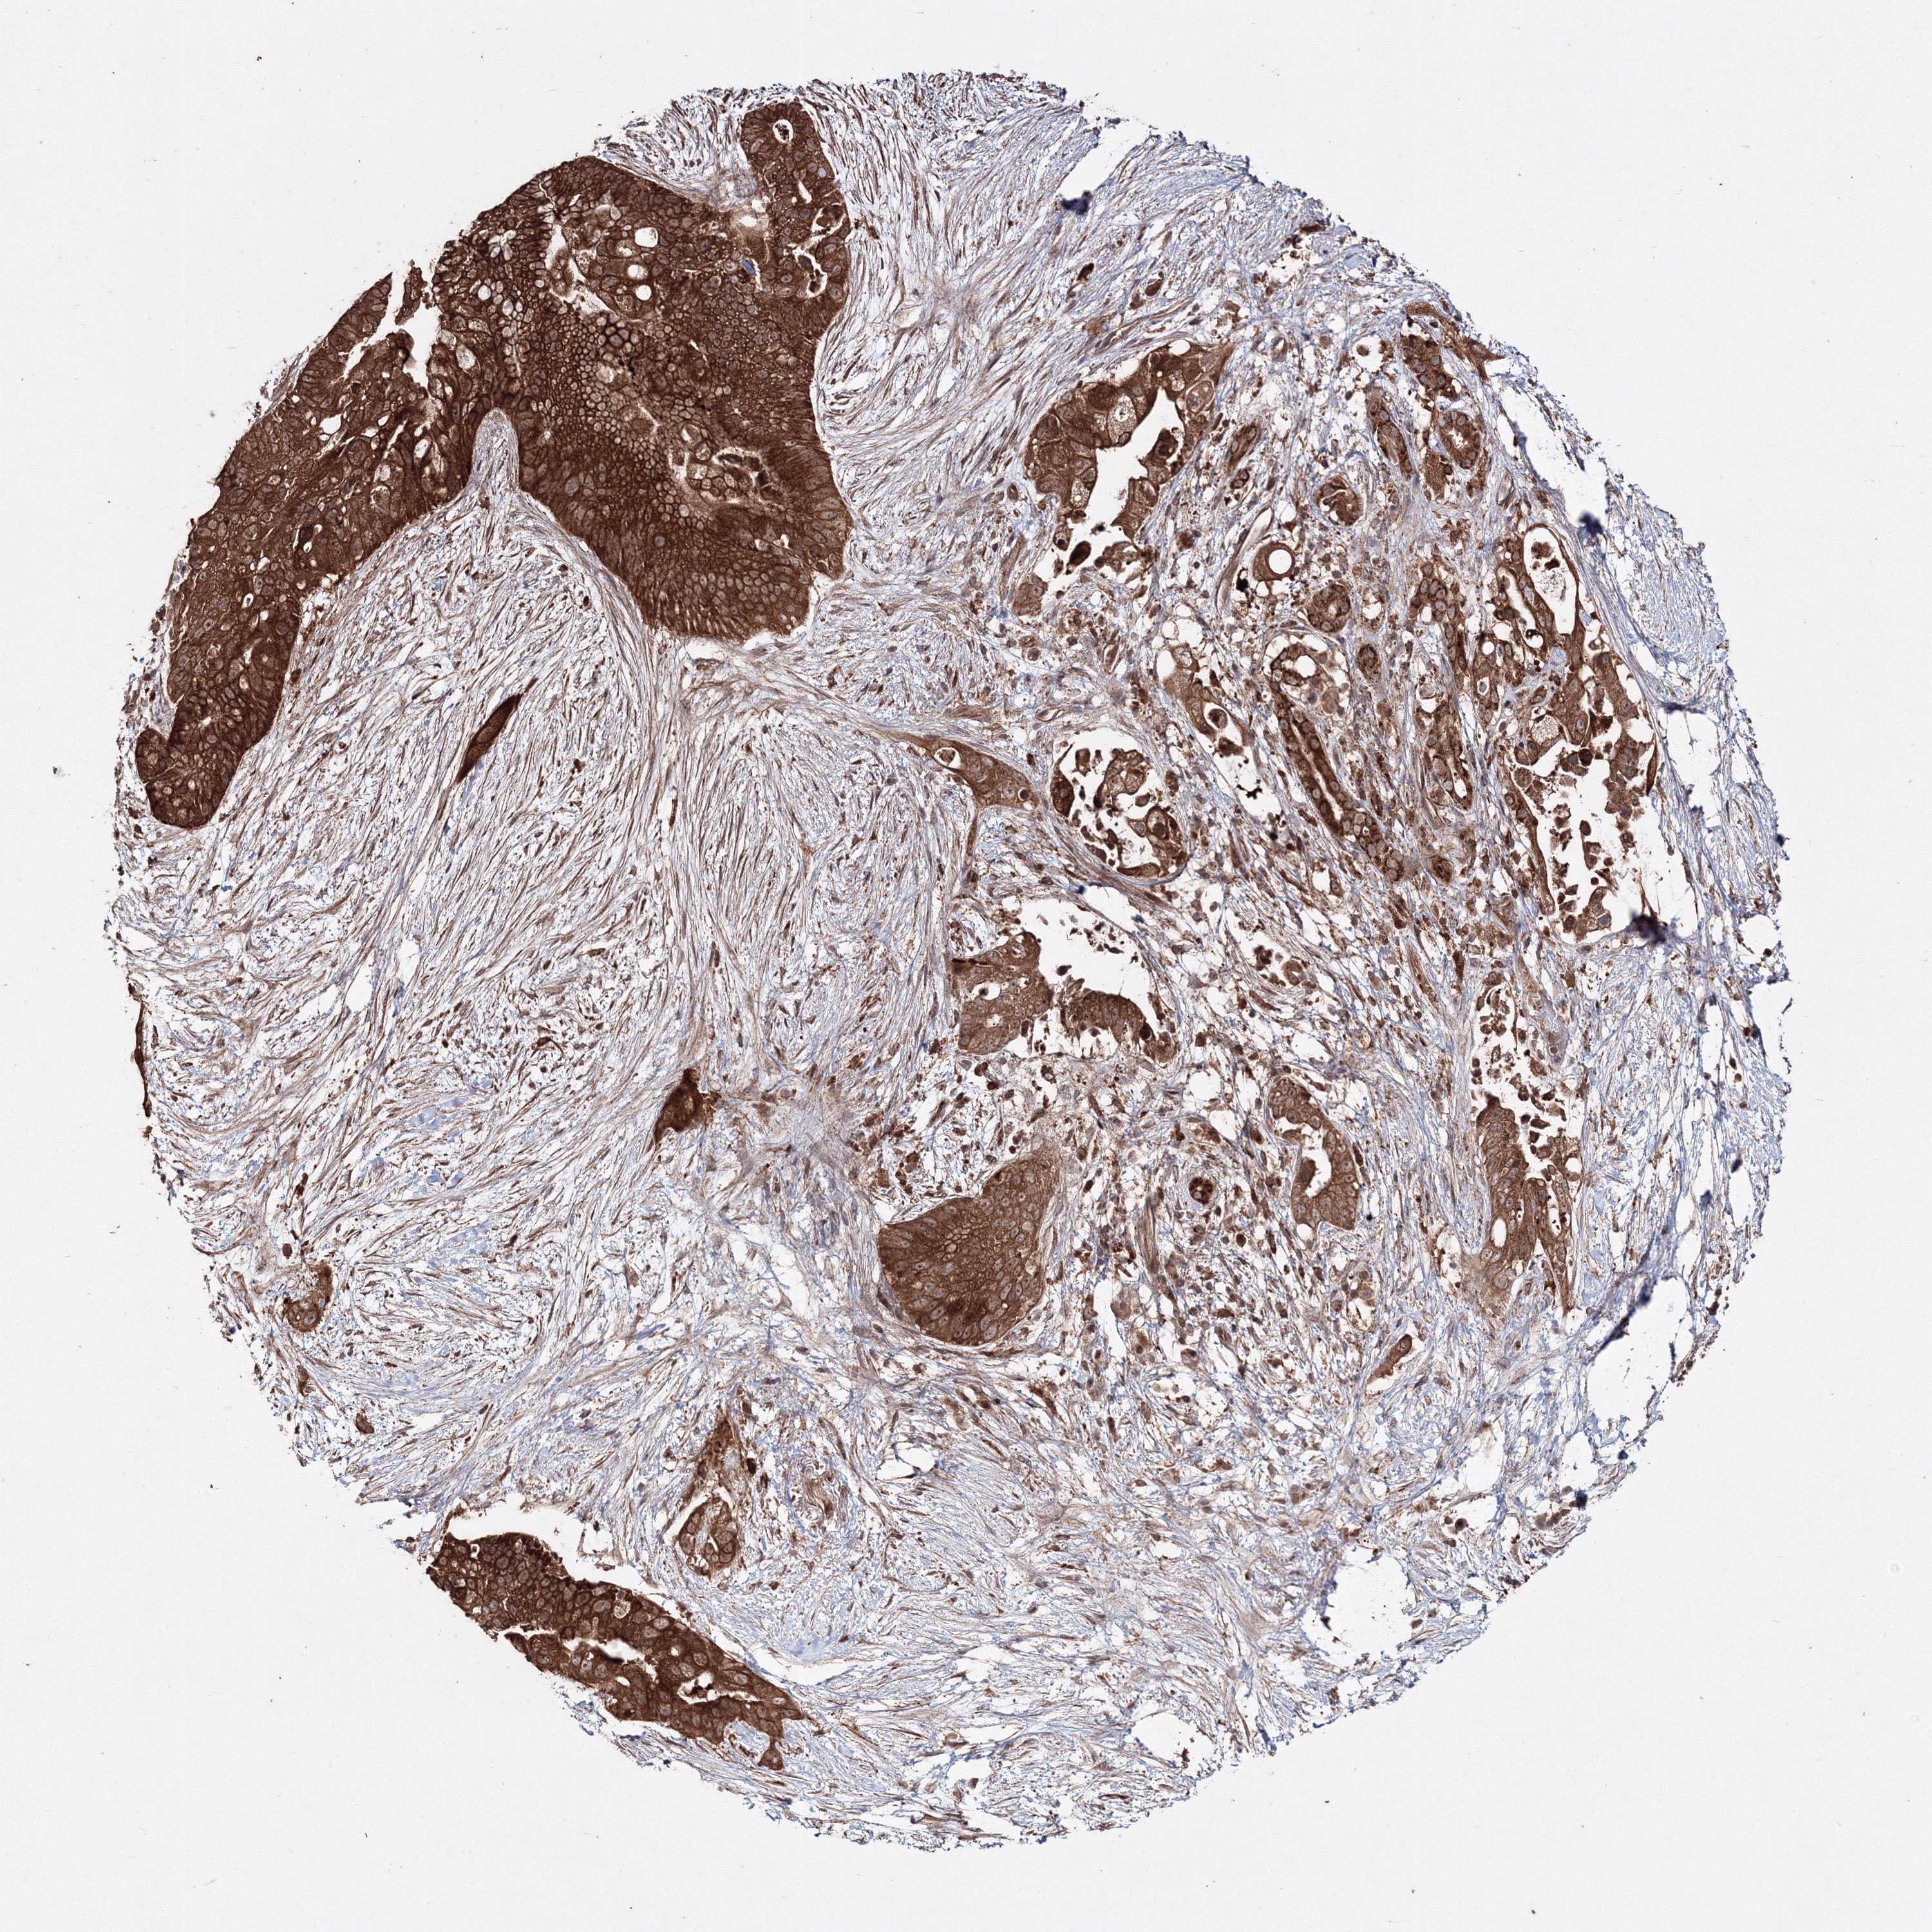

PANCREATIC CANCER - Protein expressioni

A mouse-over function shows sample information and annotation data. Click on an image to view it in a full screen mode. Samples can be filtered based on level of antibody staining by selecting one or several of the following categories: high, medium, low and not detected. The assay and annotation is described here.

Note that samples used for immunohistochemistry by the Human Protein Atlas do not correspond to samples in the TCGA dataset.

Antibody stainingi

Antibody staining in the annotated cell types in the current human tissue is reported as not detected, low, medium, or high, based on conventional immunohistochemistry profiling in selected tissues. This score is based on the combination of the staining intensity and fraction of stained cells.

Each image is clickable and will lead to virtual microscopy that enables deeper exploration of all samples and also displays staining intensity scores, fraction scores and subcellular localization as well as patient and tissue information for each sample.

Antibody HPA037525

Antibody HPA037526

Staining

High

Medium

Low

Not detected

Intensity

Strong

Moderate

Weak

Negative

Quantity

>75%

75%-25%

<25%

None

Location

Nuclear

Cytoplasmic/membranous

Cytoplasmic/membranous,nuclear

Adenocarcinoma, NOS